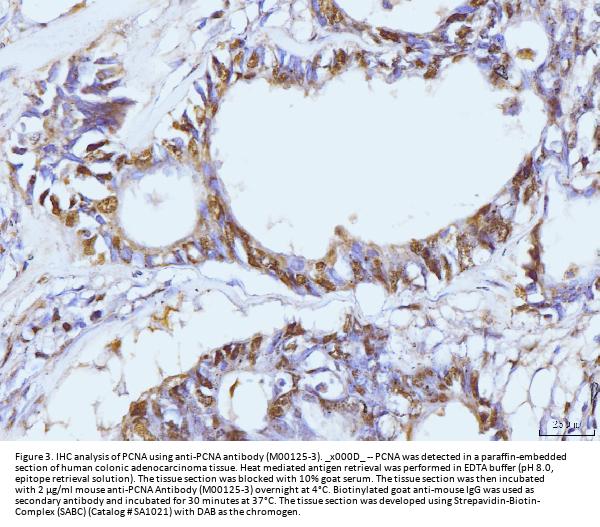

Immunohistochemistry(Paraffin-embedded Section), 2-5 μg/ml, Human, Mouse, Rat

Boster Bio Anti-PCNA Antibody Picoband® (monoclonal, 2G2) catalog # M00125-3. Tested in Flow Cytometry, IF, IHC, ICC, WB applications. This antibody reacts with Human, Mouse, Rat. The brand Picoband indicates this is a premium antibody that guarantees superior quality, high affinity, and strong signals with minimal background in Western blot applications. Only our best-performing antibodies are designated as Picoband, ensuring unmatched performance.